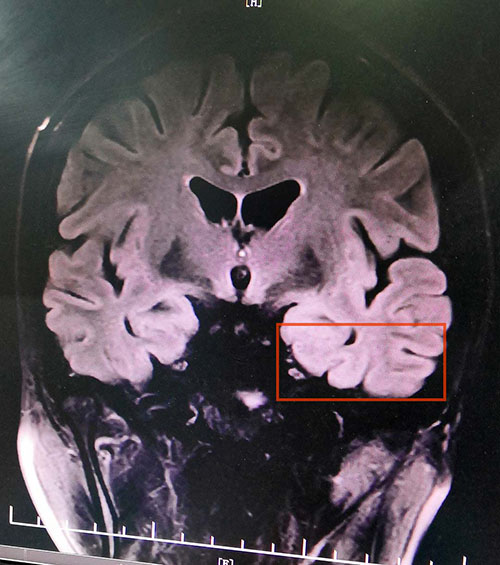

来院后,脑电监测崔丽华主任应用先进的美国尼高力长视频脑电图仪为李小琴做了24小时脑电监测。在监测中,从事临床及脑电图工作30余年的崔主任敏锐地发现了异常脑电波,脑电监测起源提示为左侧起源为著。另头颅MR+MRS示:MRS提示双侧海马Cho峰升高,右侧NAA/Cr+Cho=0.44;左侧NAA/Cr+Cho=0.55。

▲患者海马、颞叶病灶区

蓝十字脑科医院功能神经外科专家、中国规范化癫痫外科的创始人之一杨忠旭博士查看了患者各项检查报告并听取相关病情汇报,综合多项检查并结合病史,李小琴确诊为:难治性癫痫。

杨忠旭博士说:这类难治性癫痫可以行“癫痫病灶切除术”外科手术治疗,但是必须对癫痫病灶进行精准定位。所幸,经过磁共振检查结合脑电检查等可以明确患者癫痫病灶位于海马、颞叶部位。